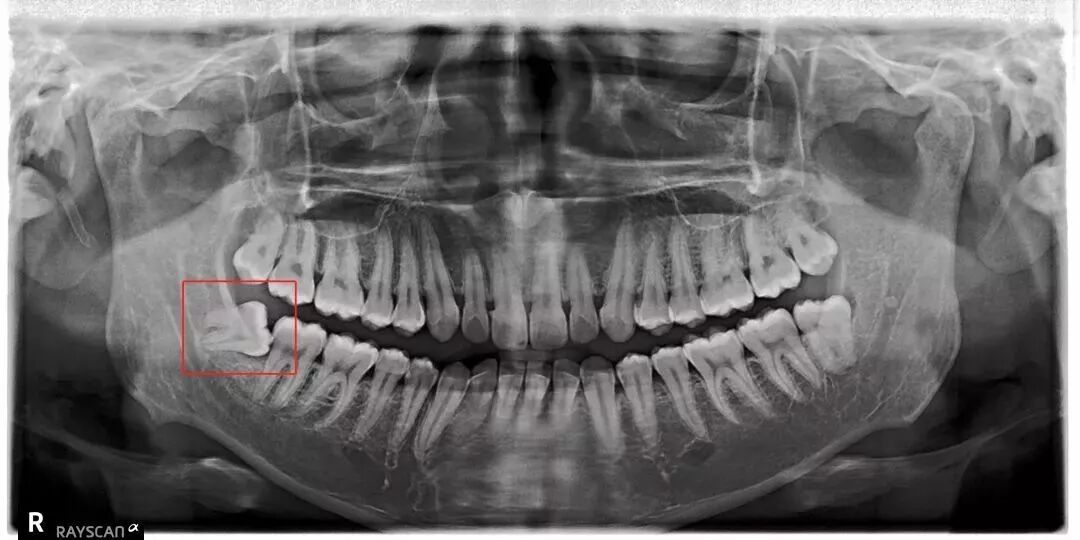

站没站相

智齿从出生的那一刻就注定了

他不同于其他牙齿的一生

他能各个位置、各种角度窜出来

把前一颗牙齿顶坏:

把整副牙齿挤歪:

一部分智齿学聪明了

学会了藏身

他们躲到牙龈底下躲着

甚至直接躲到了骨头底下

左划看看他们真实的模样